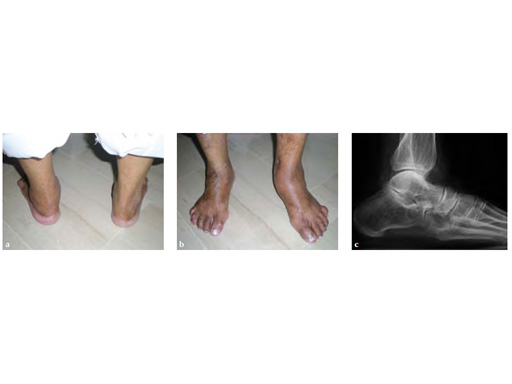

Case 2: 67-year-old white female

Case provided by Juan Bernardo Gerstner Garcs, Cali, Colombia

Stage II of her left posterior tendon dysfunction and tarso/metatarsal, instability visible on x-ray (see Fig 1a-c).

A medializing calcaneal osteotomy was performed and fixed with two 6.5 mm HCS, a flexor hallucis longus transfer to her navicular is secured with an interference 7 mm screw and a lapidus procedure fixed with two crossing 4.5 HCS (see Fig 2a-b).